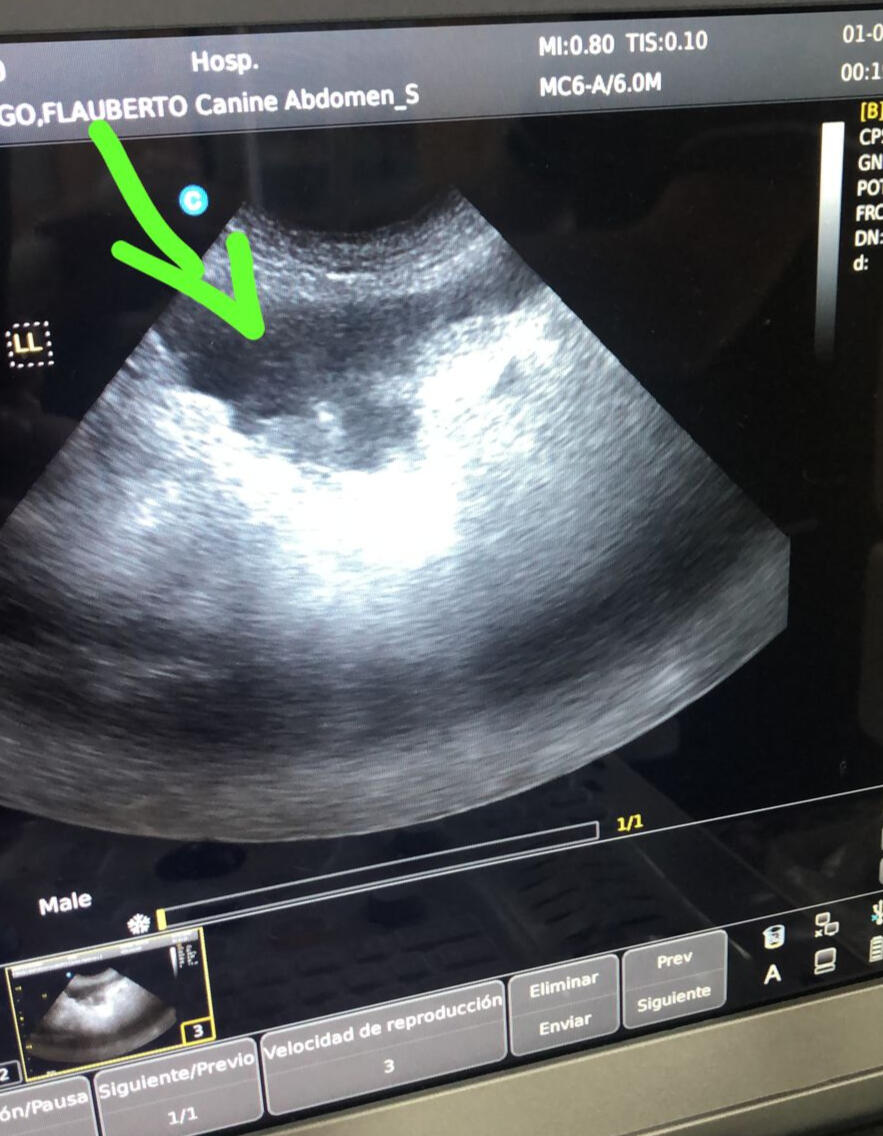

UNA PEQUEÑA HISTORIA DE FUERZA, VALOR Y AMOR…Flaubert, un pequeño que hasta esta historia no me había enterado que es un perrito de raza Lhasa Apso, llevaba una vida normal al lado de su familia y personas que lo consentían y lo querían demasiado, quizá mas de lo que el pensaba o sentía. (Aunque ellos saben y sienten todo lo que nosotros pensamos y también sentimos).Creo firmemente que las cosas pasan por algo, y por ello la vida cambió de un momento a otro para él: ingirió 2 pedazos de esponja parecida a las bolas de desestrés que se compran normalmente en mercados y abacerías, de lo cual la familia hasta ahora no saben el origen de la misma. Lo único que se pudo evidenciar aquel fatal día fue que vomitó un tercer objeto mucho mas grande, suficiente para vomitarlo y dejarlo como evidencia de aquello. Sin embargo, nunca su familia se enteraría sino ya hasta los primeros síntomas, que no demoraron muchos días hasta aparecer.Posteriormente, empezó un proceso lento pero constante de malestar, sobre todo evidenciando falta de apetito. Su familia pensó que quizá es algún problema pasajero, hasta que pasaron unos pocos días con el mismo pesar.Lo primero que pensé es llevarlo a la clínica veterinaria "D' horror", la cual fue la causante de un gran problema posterior. Lamentablemente la ética fue supeditada quizá al dinero y pensar en hacer un buen diagnostico y una buena cirugía no estaban en sus planes.Flaubert entro un día domingo a la veterinaria con mucha preocupación por no saber su situación. Sin embargo, luego de un pésimo diagnostico, únicamente fue recetado con “pastillas para una posible gastritis”. Nunca, y a pesar de una insistencia mía por hacerle unos estudios mas (pues parecía un suceso muy raro), no se realizaron ecografías/rayos x que evidencien algo mas. Flaubert lamentablemente entro un día lunes nuevamente a la clínica y no fue sino luego ya de una ecografía que se determinó que era necesario una cirugía urgente pues se encontraron aquellos objetos, pero no solo eso: liquido libre en abdomen, es decir, ya un proceso de Peritonitis en curso.Lamentablemente en esta clínica, la primera cirugía pareció algo normal, un proceso común que siempre se hace y no se complica con el tiempo. La familia esperó como algo normal los sucesos relacionados como la recuperación respectiva de Flaubert. Sin embargo, nuevamente el mismo medico, el único “competente” de la clínica, determina que es necesario otra cirugía pues existe liquido libre en el abdomen. Cabe aclarar, que nunca se tomaron todas las constantes vitales, nunca se tomo una nueva ecografía, y se dosificó doblemente medicamentos para el dolor como el Meloxican que luego se determinó que fue el causante de hemorragias y sangrado intestinal de Flaubert y que afectarían su recuperación. Además, los antibióticos fueron muy básicos para una infección que venia siendo muy fuerte y que iba a denotar problemas posteriores como el fallo renal que se le detectó.Los días miércoles jueves y viernes fueron muy angustiantes y tristes. Se iba de un momento a otro un ser que básicamente cometió un error. Pero había grandes sospechas de que los procesos médicos estaban siendo los peores. Todo llegó a un límite cuando la clínica a partir de una llamada, lo único que proponía fue la eutanasia. Se habían rendido sin mas, y no había, según ellos, nada mas que hacer. Sin embargo, no me quise rendir, y sabía que, si Flaubert aun quería luchar por vivir, yo tenía que hacer algo.El viernes de esa semana, Flaubert es sacado de urgencia de aquella clínica, hacia otra mucho mas profesional. En la clínica “Patas”, Flaubert es ingresado en shock, con las constantes por los aires: presión arterial cerca de 200, amarillo completamente, con liquido en todo su pequeño abdomen, completamente débil luego de mucho tiempo de no poder comer. Básicamente, un pequeño a punto de morir.Rápidamente, la acción de los médicos por estabilizarlo fue inmediata y eficaz, al punto de mantenerlo al menos esa noche un poco mas confortable ante cualquier situación. Sabía que lo podía perder, y que poco podía hacer. Sin embargo, el momento mas fuerte fue al siguiente día: cavar su tumbar ante la llamada de la clínica el sábado en la mañana para dar a conocer que se necesita una tercera cirugía pues la ecografía no fue alentadora, y al contrario el liquido estaba derramado sobre el abdomen, comprometiendo sus órganos vitales como hígado, páncreas, y riñones. Todo se veía mal. Me derrumbé… sabía que no había nada mas que hacer, pues en la anterior clínica ya le habían cortado parte del intestino a nivel del yeyuno, el cual había estado necrosado, y sentía que no podría resistir un nuevo corte del mismo ante una nueva necrosis, y que por mas suturas que se le den, estas no iban a resistir.Dicen que los milagros hay que vivirlos para creerlos. Ahora creo en ellos. Flaubert, a pesar de ser su tercera cirugía, se levantó como si nada, y lo mejor de todo es que no había necrosis del intestino, pero se descubrió algo mas: la pésima cirugía realizada en la primera clínica, pues se habían usado suturas que son normales en musculo, no en áreas tan delicadas, y entre otras cosas, la demasiada extensión/distancia entre suturas. Creo que un hilo de esperanza creció en su familia.Los días posteriores fueron duros, y constantemente llenos de inseguridad sobre lo que iba a pasar: todos los días Flaubert era sometido a Hemogramas y casi todos los días a ecografías y análisis químicos. De allí, se quedo presente que el Hematocrito, las Plaquetas y la Albumina en sangre eran bajos constantemente, y los Neutrófilos y Leucocitos que son los que indican la infección, eran siempre altos, esto por la Peritonitis que llevaba tanto tiempo, además de la inflamación de su intestino, el fallo renal producto de la mala medicación en la clínica anterior y la anemia luego de varios días sin comer. Hasta que llegó el momento: se necesita una transfusión de sangre, y la desesperación empezaba a tomar forma.Como se espera siempre, luego de la misma, los indicadores hematológicos mejoraron, pero había que seguir peleando, en los días posteriores pues nuevamente caían: la infección aun ganaba terreno, a pesar del uso de un potente antibiótico, y los cuidados respectivos. Sin embargo, la Fe no caía, y cada noche antes de dormir pensaba que las cosas iban a cambiar.Los días iban y venían. Flaubert luchaba fuerte y solo demostraba que no se quería ir. Mostraba siempre la valentía de alguien que amaba la vida a pesar de todo. Y a pesar de que tuvo su cuarta cirugía nuevamente para volver a suturar pequeñas fisuras aún en su ya golpeado intestino, el sufrimiento por ver su recuperación generaba una ansiedad constante. Había bajado su peso de 8.5kg a 6.5kg en algunos días.Parecía que las cosas tenían un tono blanco negro: a veces buenas, a veces malas. Parecía que la infección había llegado para quedarse y eso desalentaba a los médicos y sobre todo a su familia que sentía que lo iban a perder y que todo lo recorrido hasta aquí había sido en vano. Hasta que llegó un momento más: era necesario una segunda transfusión.Un segundo perrito fue usado para ello. Los dos fueron realmente unos buenos canes. Pero era necesario hacer pruebas cruzadas para ello, y gracias a Dios, se pudo contar con esa sangre, pero a pesar de que ese día no pasó mayor cosa, 100ml de sangre fueron rechazadas a la noche, y una llamada de la clínica determinó un segundo momento de derrumbe de todos: si la efusión/rechazo de la sangre continuaba, Flaubert tenía sus horas contadas. La ecografía era clara: la sangre estaba en el abdomen. Esa noche, solo se que mi corazón no estaba conmigo, sino en la clínica con él, y que a pesar de que no lo iban a permitir, deseaba pasar la noche junto a él, de forma que si era la ultima vez que lo veía, pues que sepa que estaba con él hasta el final.Los médicos esa noche pasaron los 150ml restantes de la transfusión deseando y rogando que el cuerpo ya débil de Flaubert por varios días de anemia, infección e inflamación, aun pueda resistir. Quizá apoyados en un hilo de esperanza al ver que él no deseaba rendirse. Solo sé que no deseaba ver el celular en la mañana, pues pensaba encontrar lo que podía ser a ese momento: su amigo murió esta noche... Lo bueno es que, su cuerpo, en una especie de milagro, lo recibió finalmente y durante esa noche no rechazo esa sangre, y al contrario su cuerpo lo recibió: ¡se salvó!Durante los días posteriores, a pesar de aun luchar contra la infección, se veía que Flaubert amaba vivir, y quería compartir un tiempo más en este mundo que de por sí es demasiado cruel.Mis compañeros de todos los días fueron los glóbulos blancos y rojos. Que baje la infección y que suba el hematocrito, y sobre todo que coma, pues no deseaba y era una lucha verdadera para que logre un bocado de alimento.Felizmente llegó el día de su alta. ¡Un día que no olvidaré jamás… cuanto anhelo, cuanta lucha! ¡Se logró!He tomado esto del Facebook personal de la doctora encargada del milagro y medico en jefe de la clínica “Patas”, Dra. Paola Alvarado Dávila, orgullosamente alumna destacada de la Universidad de Cuenca:“Este es Flaubert, canino de 7 años que acude a consulta el día 01 de marzo con un cuadro grave de peritonitis con un tiempo de evolución aproximado de 8 días.

“Flau” es un shi tzu que ingreso a consulta por presentar un cuadro muy grave de peritonitis, el tutor refiere que paciente estuvo hospitalizado en otro centro veterinario desde hace 1 semana aproximadamente por presentar un cuadro de vómitos agudos, al no haber mejoría piden interconsulta con el ecografista, en donde observan 2 cuerpos extraños en la porción de intestino delgado (yeyuno), por lo cual deciden extraer estos cuerpos mediante cirugía, tras dos cirugías fallidas, y con (criterio de eutanasia), paciente ingresa a hospitalización en donde no solo vemos un cuadro grave de peritonitis, sino también una lesión renal aguda y pancreatitis. Con todo el amor del mundo lo recibimos, lo cuidamos, hicimos una tercera cirugía en donde pudimos evidenciar que las suturas de una “enteroanastomosis” habían fallado nuevamente, para poder corregir dicha falla, pasando por 2 transfusiones sanguíneas, exámenes de sangre diarios para su valoración médica.